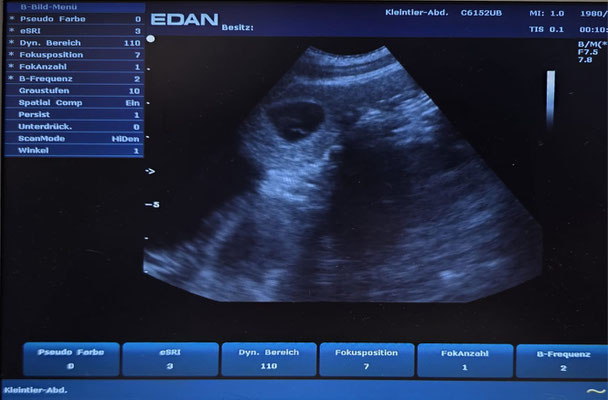

Am 02.09.25 waren wir mit unserer Lillifee zum Ultraschall und was soll ich sagen, wir sind Schwanger